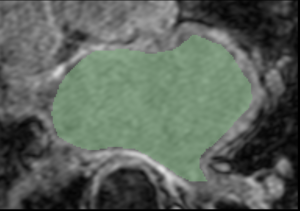

Example 4

CAMRA N26 2 LGE.png

CARMA N26 2 Endo.png

Cropped MRI image overlaid with the algorithm-defined blood pool. Expert manual segmentations (white) overlaid with the algorithm-defined blood pool (green).

Note: The last segmentation (red) was derived from an image in the atlas; the other segmentations (green) were derived from similarly-cropped images, not in the atlas.